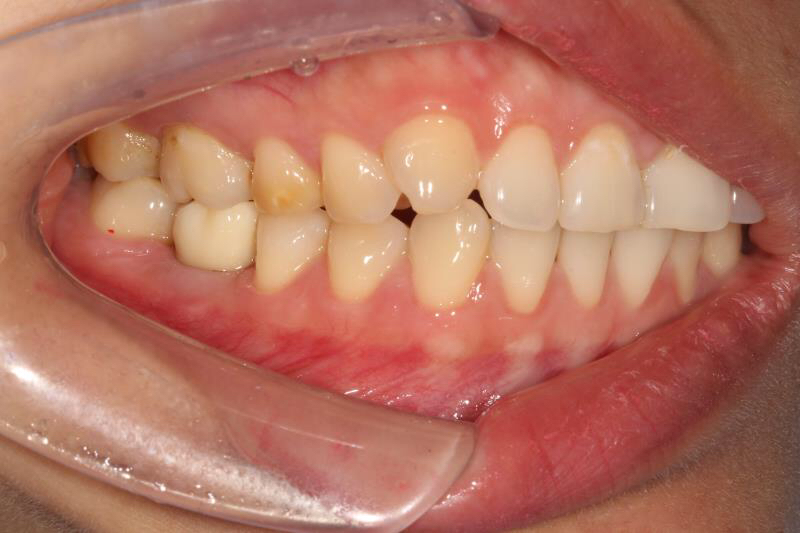

今天给大家介绍一个单颗后牙种植+局部正畸联合治疗病例。

患者年轻女性,后下6残根,因未及时修复,5、7号牙向6号牙倾斜,导致了修复空间不足。按照常规治疗方案,会损伤两侧的健康牙齿,得不偿失,所以我们为她采用了正畸+种植联合治疗方案。